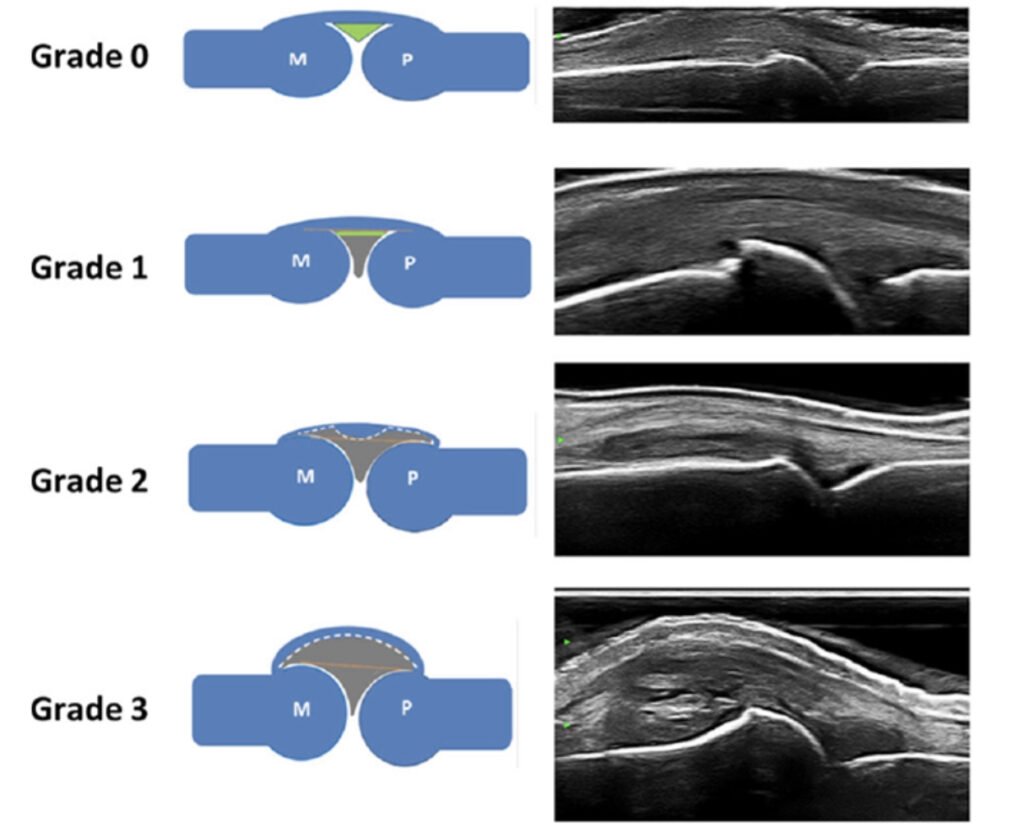

2.超音波検査

当然このような状態になってしまっては進行しているということです。リウマチは早期診断が大切な訳で近年では超音波検査やMRI検査で滑膜炎の状態を診ることが重要になります。

特に超音波検査は簡便鋭敏でパワードプラ法(血流信号)による炎症シグナルのグレード分類が2017年に提唱されるようになりました。治療効果を診る上でも超音波検査は有用で、数ヶ月に1回超音波検査を行い炎症状態が安定しているか診ることが重要です。

(2017年)

(2017年)

一度効いた薬も数年で効果が落ちることもあるため、2ヶ月毎の血液検査と滑膜炎の状態を超音波検査で診ていくことも大切になります。

具体的には早い時期から薬物療法を開始し最高用量を使用しても炎症の制御が不十分であれば生物学的製剤を併用し、速やかに臨床的”寛解”までコントロールする必要があります。寛解の状況把握は今まで血液データのみでしたが、超音波検査装置の開発により簡単完全に30秒で検査が可能となりました。